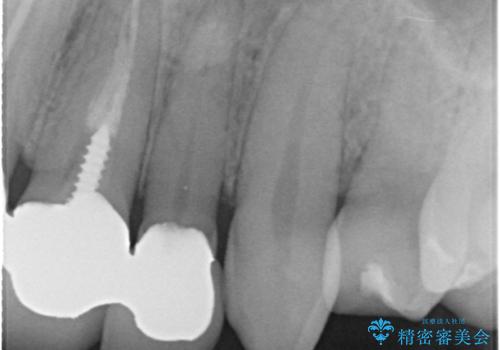

以前に装着されていたものは全て連結されており、清掃性があまり良くありませんでした。

一つ一つを独立したかぶせ物を装着することで、フロスも可能になり、清掃性が向上しました。

前歯の合計6本をオールセラミッククラウンにする計画としました。